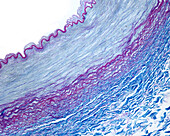

13416586 - Aorta tunica media and adventitia, light micrograph

12634941 - Aorta, tunica adventitia and media, LM

12634940 - Aorta, tunica adventitia and media, LM

12634939 - Aorta, tunica adventitia and media, LM